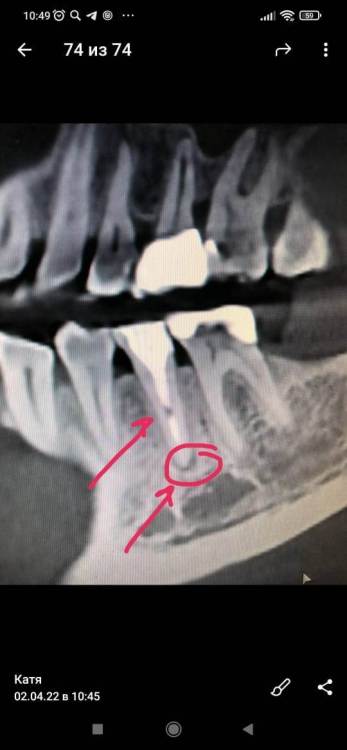

Здравствуйте! По  рекомендации   стомотолога -ортопеда (  решался  вопрос  о  постановке  коронки  на  этот   зуб) мне стоматолог-терапевт провел эндодонтическое лечение периодонтита  в   мертвой "пятерке" на  нижней   челюсти  справа. Провел  фиксацию внутриканальным штифтом и пломбирование корневого канала  зуба методом   горячей гуттаперчи. Сделала   КТ   на  следующий  день, снимки  прикладываю. Появились  вопросы   по  снимкам -что   означает  черное  пятно   в  нижней  трети  канала  после   перепломбировки? И,  как  показывает   снимок,  у  корня   зуба так  воспаление  и  не  ушло. Стоматолог - терапевт принял   решение сразу   перепломбировать  канал, с  установкой   постоянной  пломбы.  Я  думала,  что  мне  поставят   временну  пломбу  ,  и  я  несколько  раз   еще  похожу  на  лечение   к  доктору... Но   доктор  сказал,  что  типа   воспаление    само  пройдет... И  еще,  после   перепломбировки  канала,  стоматолог-ортопед  сказал,  что коронку   теперь  поставить  не  получится,  так  как   тонкие   стенки  и   низкий верх  зуба.

Здравствуйте. Первый рентгеновский снимок после лечения периодонтита делают не ранее 6 месяцев. До этого оценивать качество лечения нельзя, при условии, что вас ничего не беспокоит. Чёрное пятно в канале - просвет заполненный цементом между штифтом и корневой пломбой; либо пора в цементе.